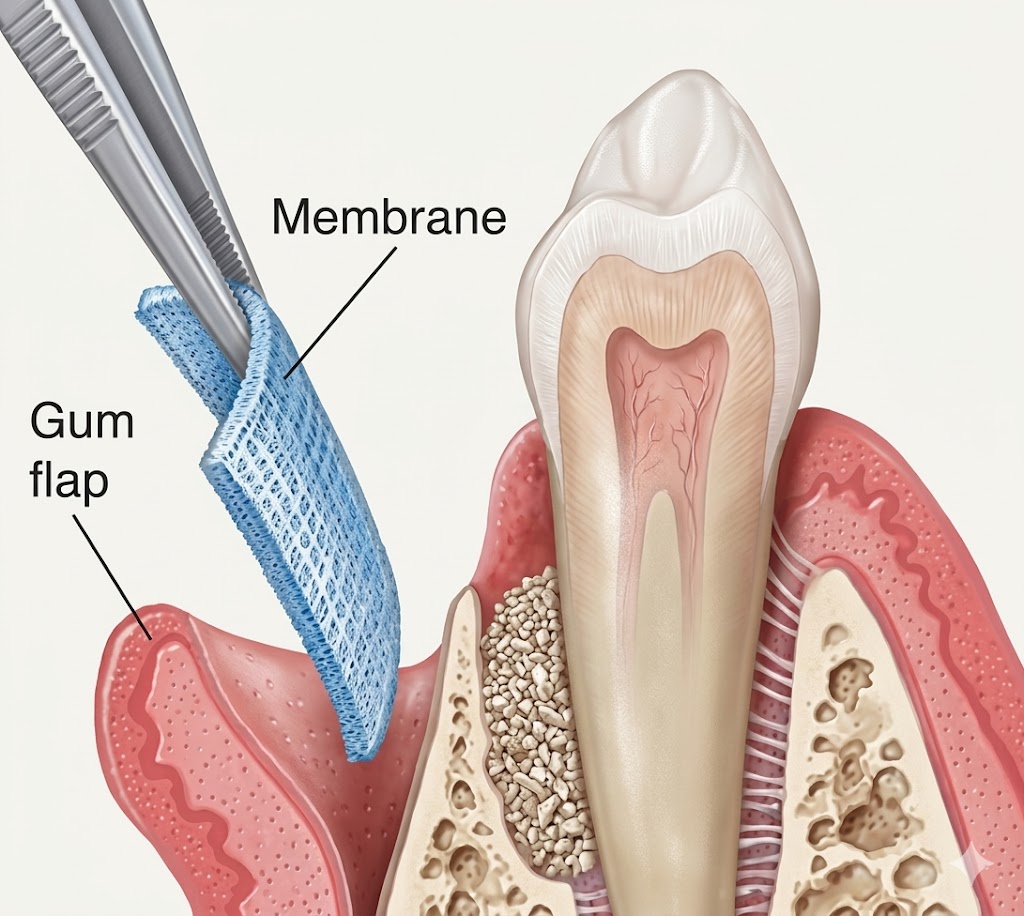

Recession exposes the tooth root, which has no enamel protection. This leads to sensitivity, especially to cold or sweet foods, and significantly increases the risk of root decay. Receded gum tissue does not grow back on its own — but it can be restored with a gum grafting procedure performed by a periodontist.